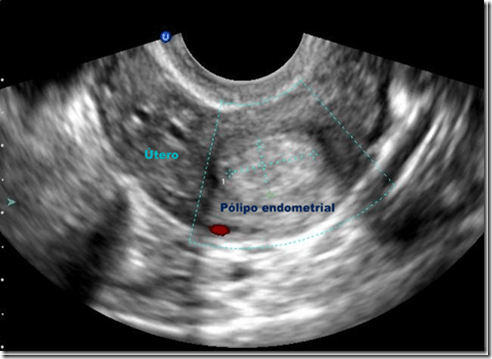

La histerosonografía es un estudio de imagen que consiste en la introducción de líquido a través del cérvix hacia el útero, realizando posteriormente un ultrasonido de la cavidad uterina. El líquido inyectado facilita la obtención de imágenes del interior del útero que no se podrían obtener solo con el ultrasonido.

Este estudio está indicado en aquellas mujeres con hemorragias uterinas anormales, infertilidad y/o abortos recurrentes. La histerosonografía puede detectar anomalías uterinas como pólipos, miomas y/o formas uterinas anormales.

Una vez inyectado el líquido se realiza un ultrasonido. A continuación se observa la imagen obtenida.